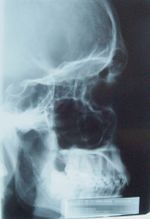

X-Ray Image of the Paranasal Sinuses, Lateral Projection

استعملت الأشعة السينية في مجالات الطب والصناعة، وكان الأطباأوالمستفيدين من استعمالها بسبب اختلاف نسب امتصاصها في الأنسجة الحية باختلاف نوع هذه الأنسجة، فاستخدمت خاصة الفلورة في التنظير الشعاعي ودراسة حركية الأعضاء، ثم استخدمت الدارة التلفزيونية في نقل الصورة المتفلورة إلى شاشة التلفاز الذي أصبح يستخدم في التنظير الشعاعي، وبذلك تناقصت كمية الأشعة اللازمة للحصول على الصورة المفلورة المتلفزة.